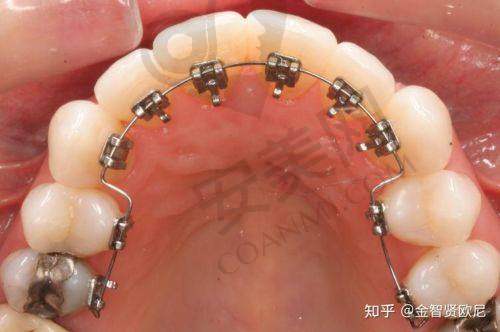

湛江柏乐口腔医院的隐形矫正技术真的特别有特色。首先,隐形牙套是采用高新科技材料制作而成的,几乎是透明的,戴在牙齿上几乎看不出来,不会影响我的美观。这对于爱美的我来说,简直是太重要了。其次,隐形牙套可以自行摘戴,这给我的生活带来了较大的便利。我可以在吃饭、刷牙的时候把牙套取下来,这样就不会影响正常的饮食和口腔卫生。而且,隐形牙套的佩戴也非常舒适,不会像传统金属牙套那样对口腔黏膜造成刺激。另外,医院还采用了数字化矫正技术,通过计算机模拟牙齿的移动过程,提前预知矫正成效。医生可以根据模拟结果对矫正方案进行调整,确保矫正成效达到至佳。这种精良的技术让我对矫正成效充满了信心。

在整个矫正过程中,复诊是非常重要的环节。医生会根据牙齿的移动情况对矫正方案进行调整。每次复诊,我都要提前和医院预约时间。到了复诊的日子,我来到医院后,还是先在候诊区等待。轮到我就诊时,医生会先检查我的牙齿情况,看看牙齿的移动是否符合预期。然后,医生会根据检查结果对牙套进行调整,或者更换新的牙套。医生还会叮嘱我一些注意事项,比如饮食方面要避免吃太硬、太黏的食物,要注意口腔卫生等。复诊的过程通常比较快,医生的操作也特别熟练。每次复诊后,我都能感觉到牙齿在逐渐发生变化,这让我非常有成就感。而且,医生和护士们的态度都非常好,让我在复诊的过程中感受到了温暖和关怀。